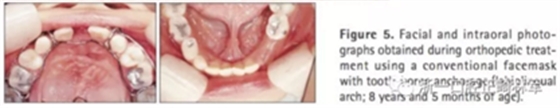

第二階段(圖5,6;表2)

面弓矯治包括在混合牙列及早期恒牙列的傳統(tǒng)牙支抗面弓及恒牙列的骨支抗面弓。由于患者曾行腭成形術(shù),為了將矯治力傳遞到上頜骨,使用唇舌弓而不是快擴(kuò)。8歲5月時開始用面弓聯(lián)合唇舌弓矯治(500g/邊,與合平面呈30°向下),持續(xù)3年6月。患者佩戴時間為12-14時/天。

上頜前磨牙萌出后取出唇舌弓,上固定矯治器以排齊上頜牙列,該階段面弓暫時停止使用。